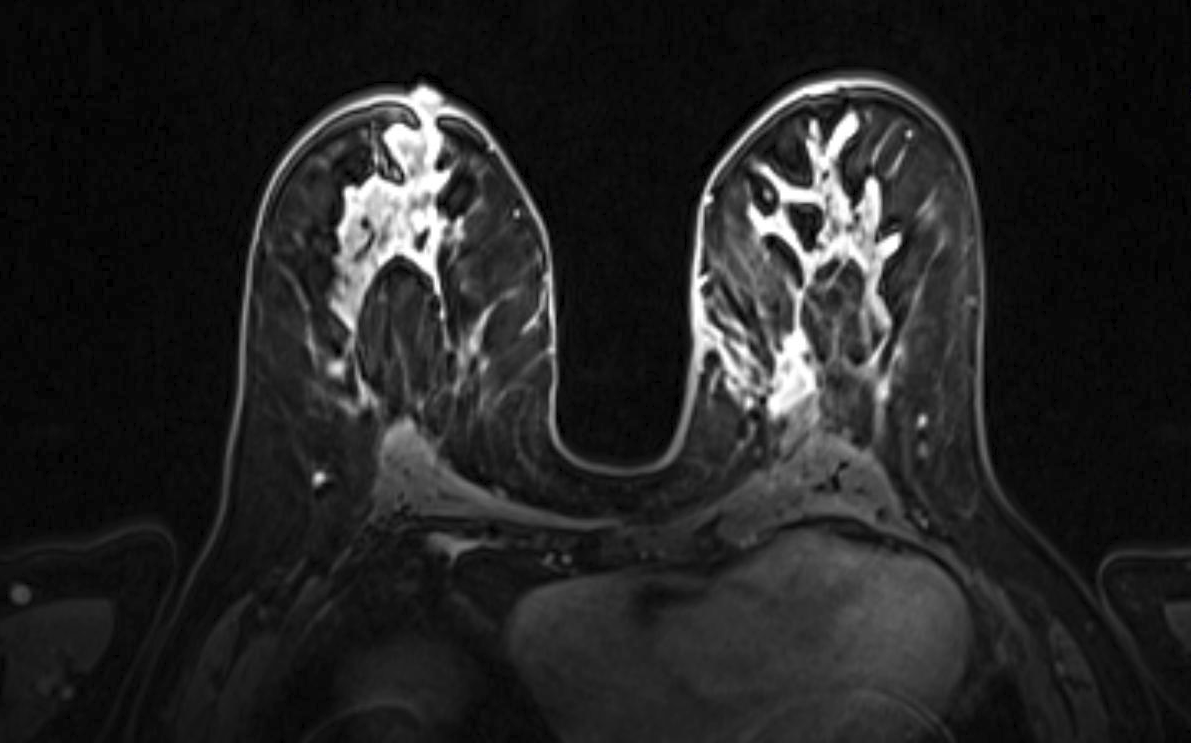

Magnetic resonance imaging (MRI) has been used as an adjunctive screening tool, mainly for women who may be at increased risk for the development of breast cancer. Example images of MRI are shown in fig. 5 with T1 contrast enhancement. MRI for screening has not been very popular in women with average risk due to concerns about the low specificity leading to additional biopsies, time and cost of technology [26]. Breast MRI sensitivity values reported in high risk screening studies range from 93% to 99%. Despite its high sensitivity, breast MRI has been reported to have variable specificity, ranging from 50% to 85% [27]. These number of sensitivity and specificity depends on the type of tumor, size of tumor, age of patient, and where it is localised.